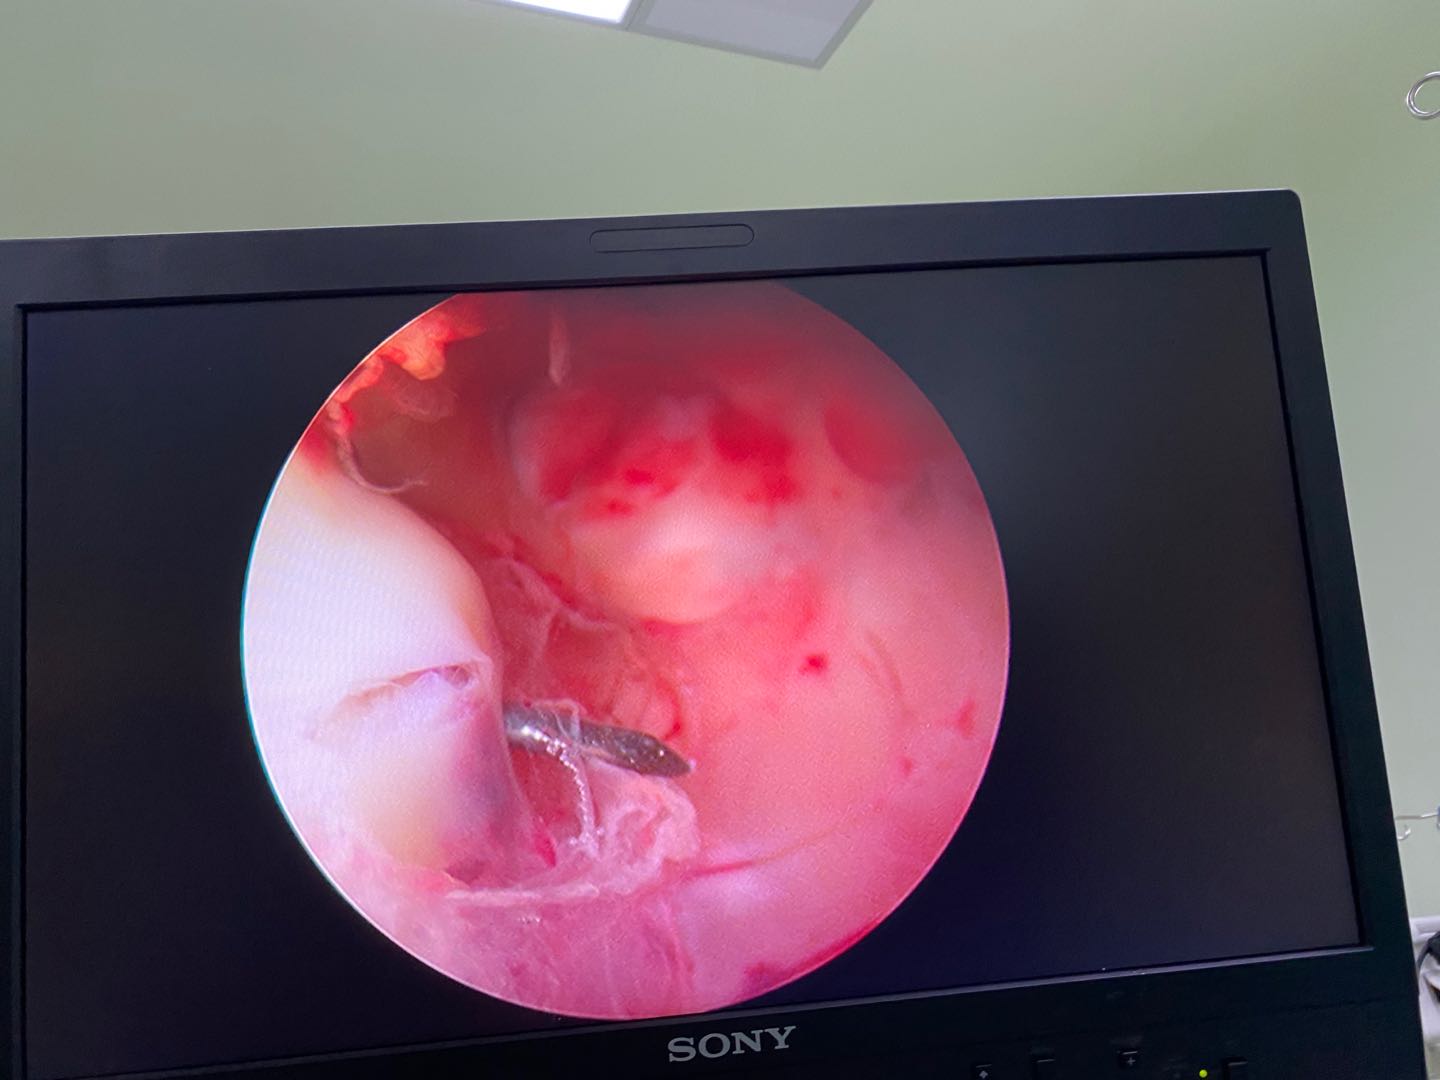

图4b 关节镜显示坐骨结节囊肿

图4c 关节镜下切除坐骨结节囊肿囊壁

4.关节镜手术仅需要2-3个0.5cm的小孔就能完成,术中出血少,在直视视野下能够彻底切除囊肿,保护神经,安全性更高,术后基本无痛,术后第二天即可下床活动,伤口愈合后基本看不见疤痕。